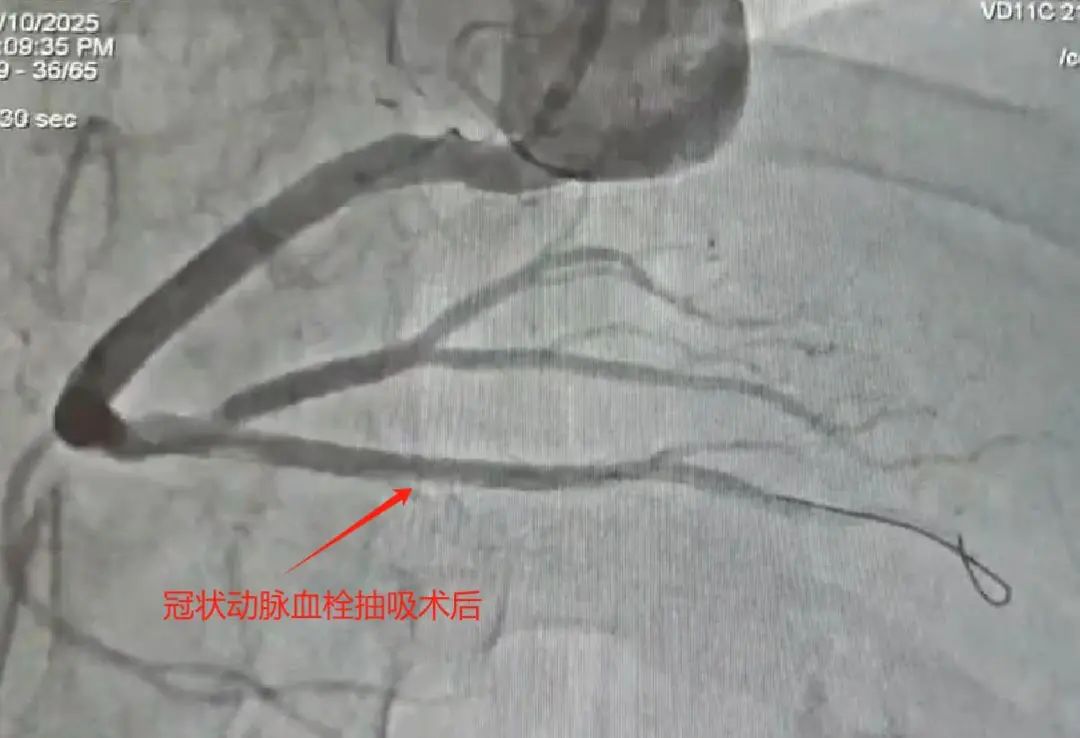

术中所见:右冠状动脉粗大,远段狭窄60-70%,后降支开口近段毛玻璃状大血栓,果断为患者实施了血栓抽吸术,抽出新鲜红色血栓,考虑患者年纪轻,右冠状动脉远段病变临界,本着无植入原则,使用药物球囊充分扩张病变,复查造影无残留血栓,治疗效果满意。